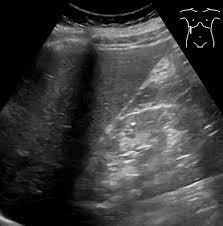

- 간경화: 간 표면의 거칠음, 크기 변화, 비장 비대 여부 등 확인